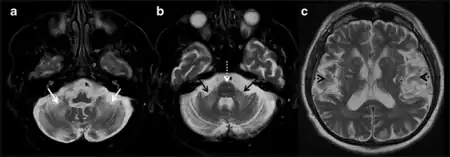

Clinical findings are divided into major and minor symptoms. Major symptoms include intention tremor and gait ataxia. Minor symptoms such as parkinsonism, short-term memory deficit, and executive function decline can further contribute to a diagnosis of FXTAS. Radiological findings are similarly divided into major and minor categories. As patients with FXTAS can have distinct brain scans from other movement disorders, a scan showing white matter lesions of the middle cerebellar peduncle is a major finding that can be attributed to FXTAS. Overall or generalized brain tissue atrophy and cerebral white matter lesions can also be minor indicators for a diagnosis.[10]